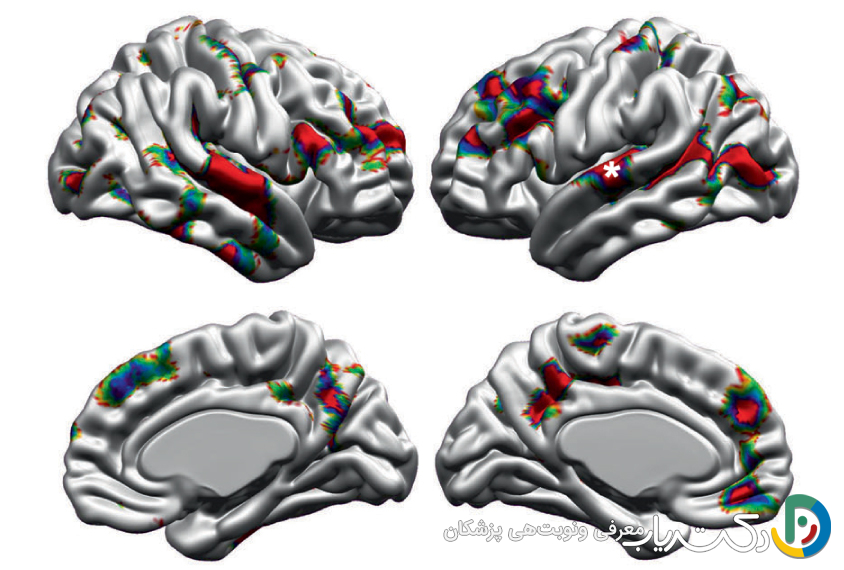

اوتیسم به مثابه یک تفاوت ساختاری در مغز

اوتیسم نتیجه یک بیماری ویروسی یا باکتریایی نیست که بتوان با دارو آن را از بین برد. این وضعیت از تعامل پیچیده عوامل ژنتیکی و محیطی در دوران پیش از تولد ناشی میشود که منجر به سیمکشی متفاوت مسیرهای عصبی میگردد. این تفاوتها بر نحوه پردازش اطلاعات، درک جهان و تعامل با دیگران تأثیر میگذارد. به بیان ساده، مغز یک فرد اوتیستیک متفاوت عمل میکند؛ این یک “سیستم عامل” متفاوت است، نه یک “نرمافزار خراب”. برای مثال، بسیاری از افراد اوتیستیک اطلاعات را به صورت جزء به کل پردازش میکنند، یعنی ابتدا بر جزئیات تمرکز کرده و سپس تصویر بزرگتر را میسازند، در حالی که افراد غیر اوتیستیک (نوروتیپیکال) تمایل به پردازش کل به جز دارند. بنابراین، تلاش برای درمان اوتیسم مانند تلاش برای تغییر رنگ چشم یا چپدست بودن یک فرد است؛ این بخشی از ساختار وجودی اوست.